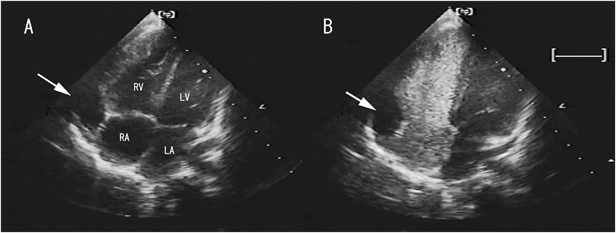

An echocardiographic study identified an anechoic lesion with a clear border located outside the right atrium (Fig. 1A). Chest contrast-enhanced computed tomography revealed a 16×14-mm lesion with the CT number of water (Fig. 2). A pericardial cyst or diverticulum of the right atrium was suspected, given the location and distinct visual features of the lesion.

Fig. 2 Contrast-enhanced computed tomography

The lesion (arrow) measured 16×14 mm, with the CT number of water (5–10 Hounsfield units).